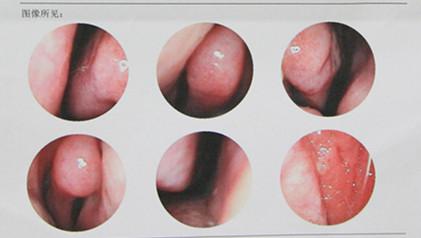

图:经德国wolf内窥镜系统检查鼻部镜像示图